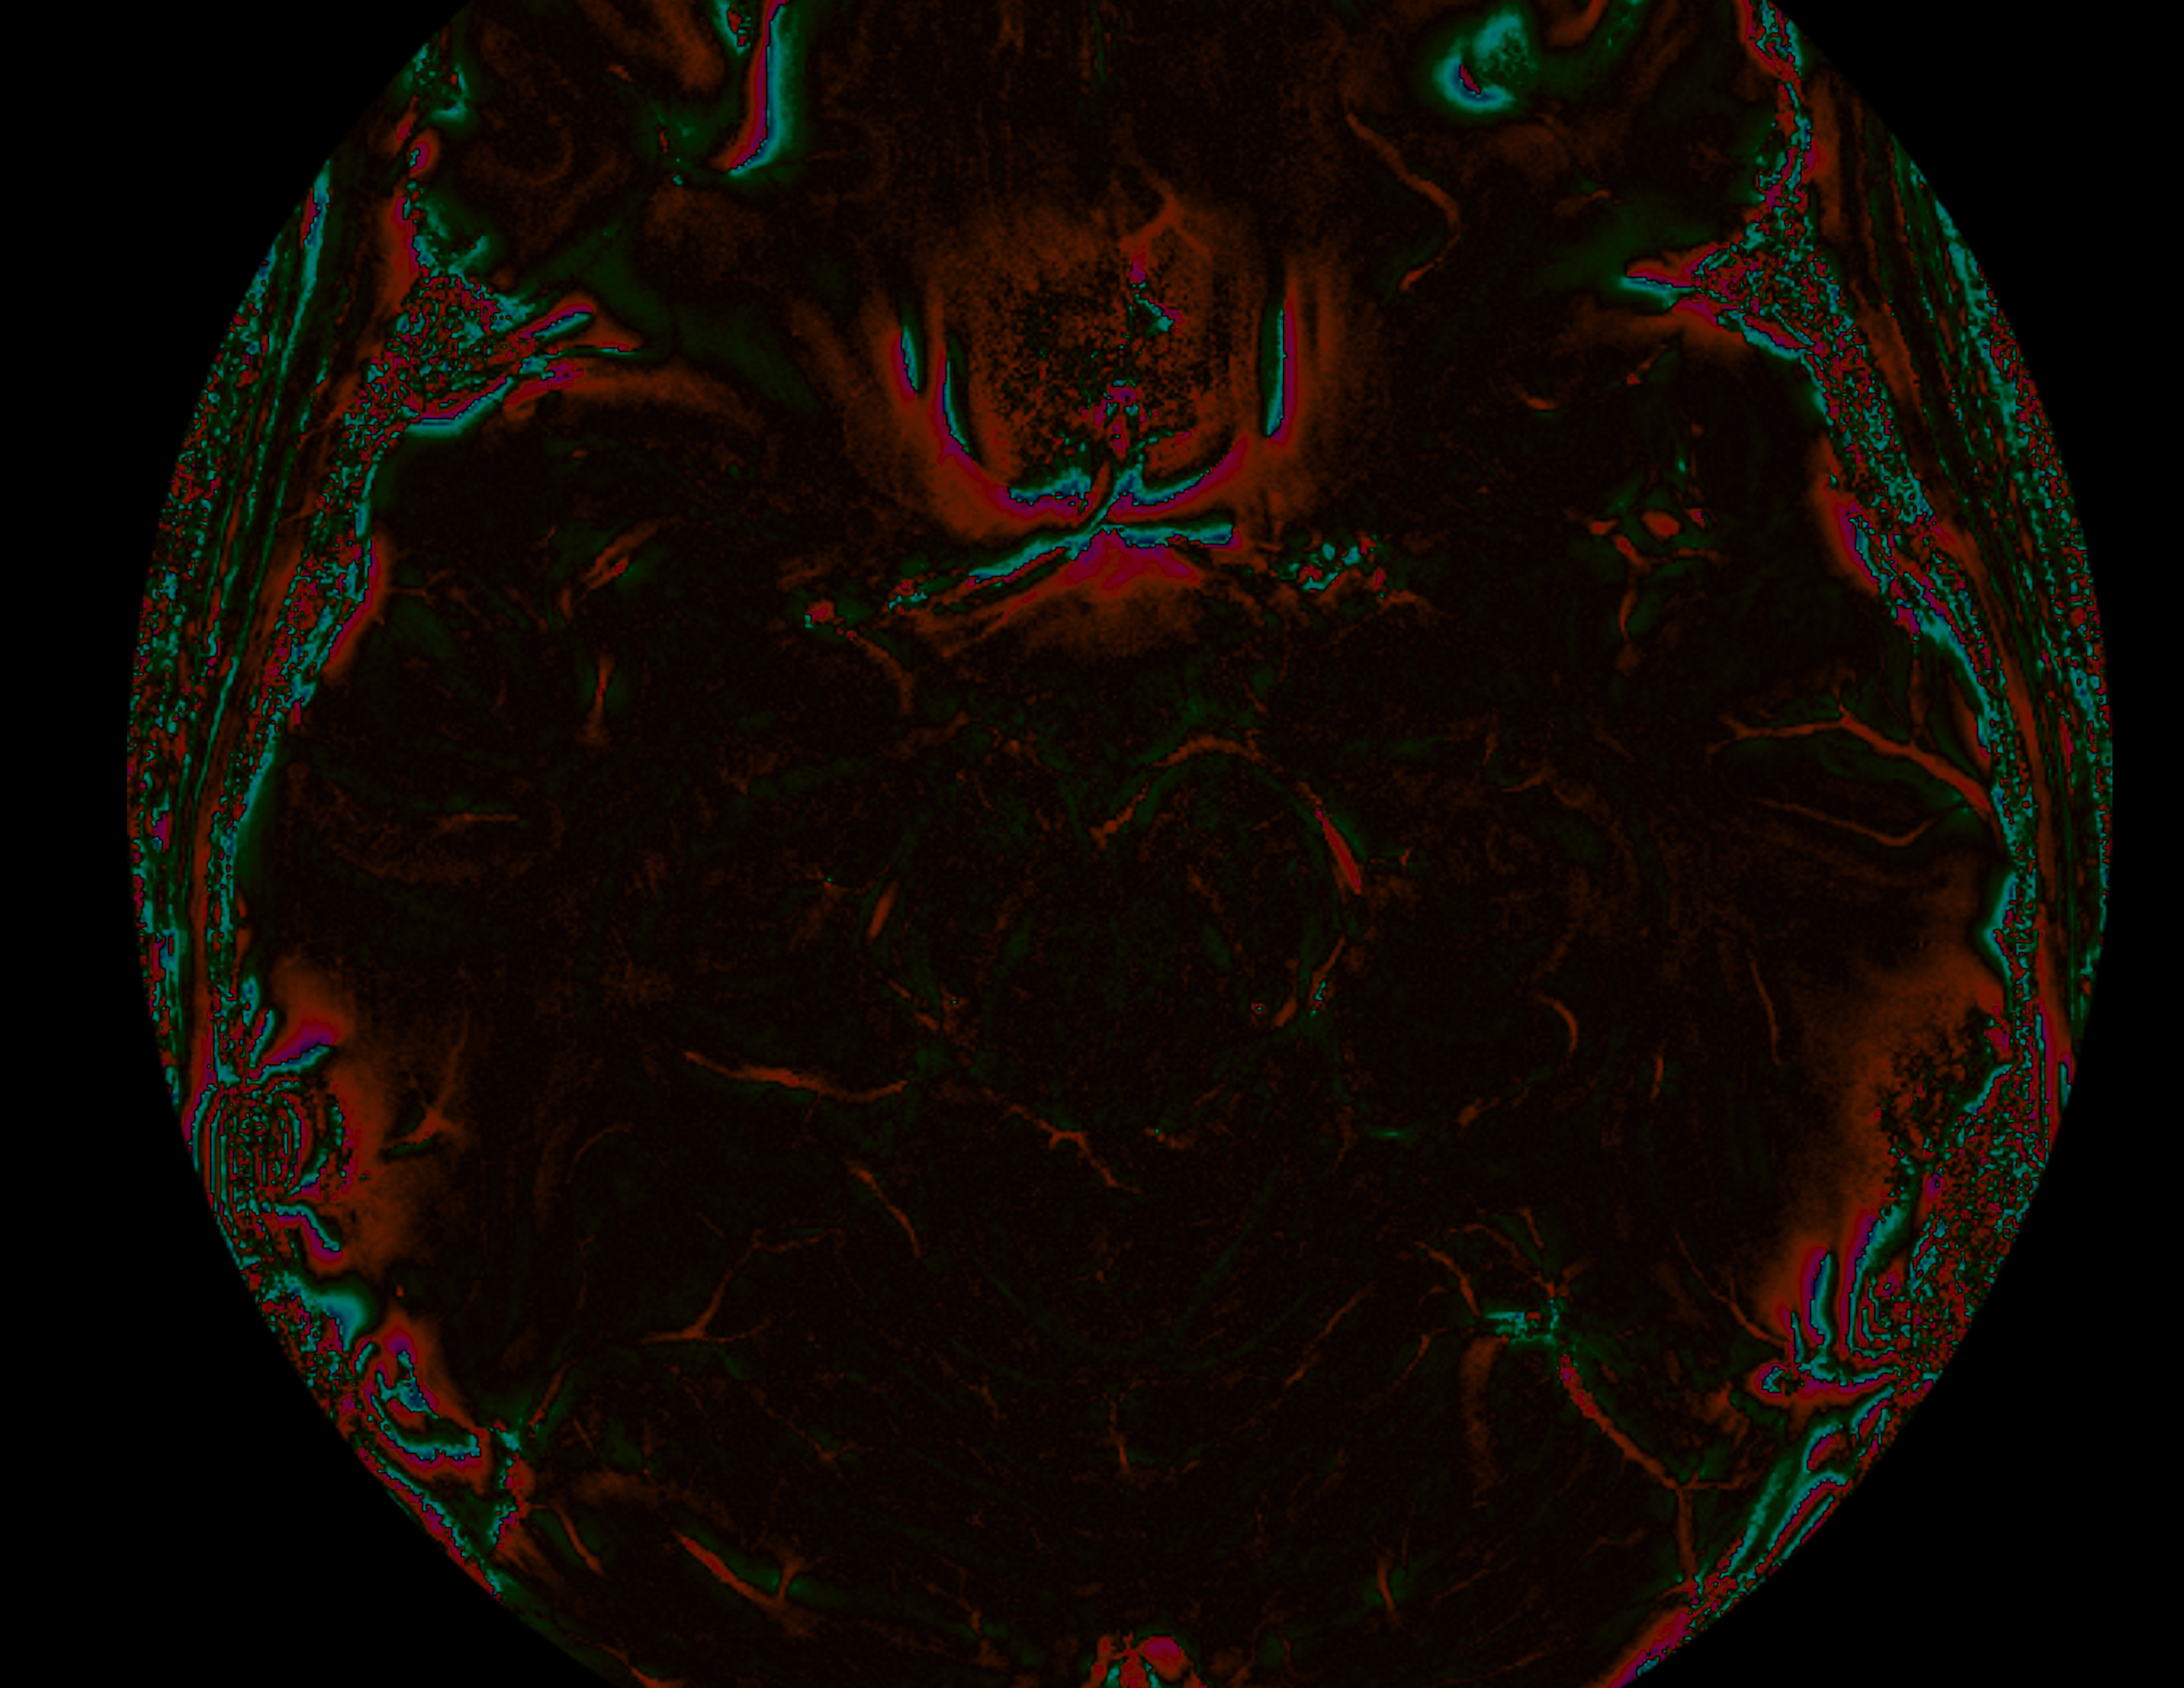

Suceptablity differences between tissues can and phase changes to the images we acquire. Here the sinus cause a beautiful rose-shaped pattern